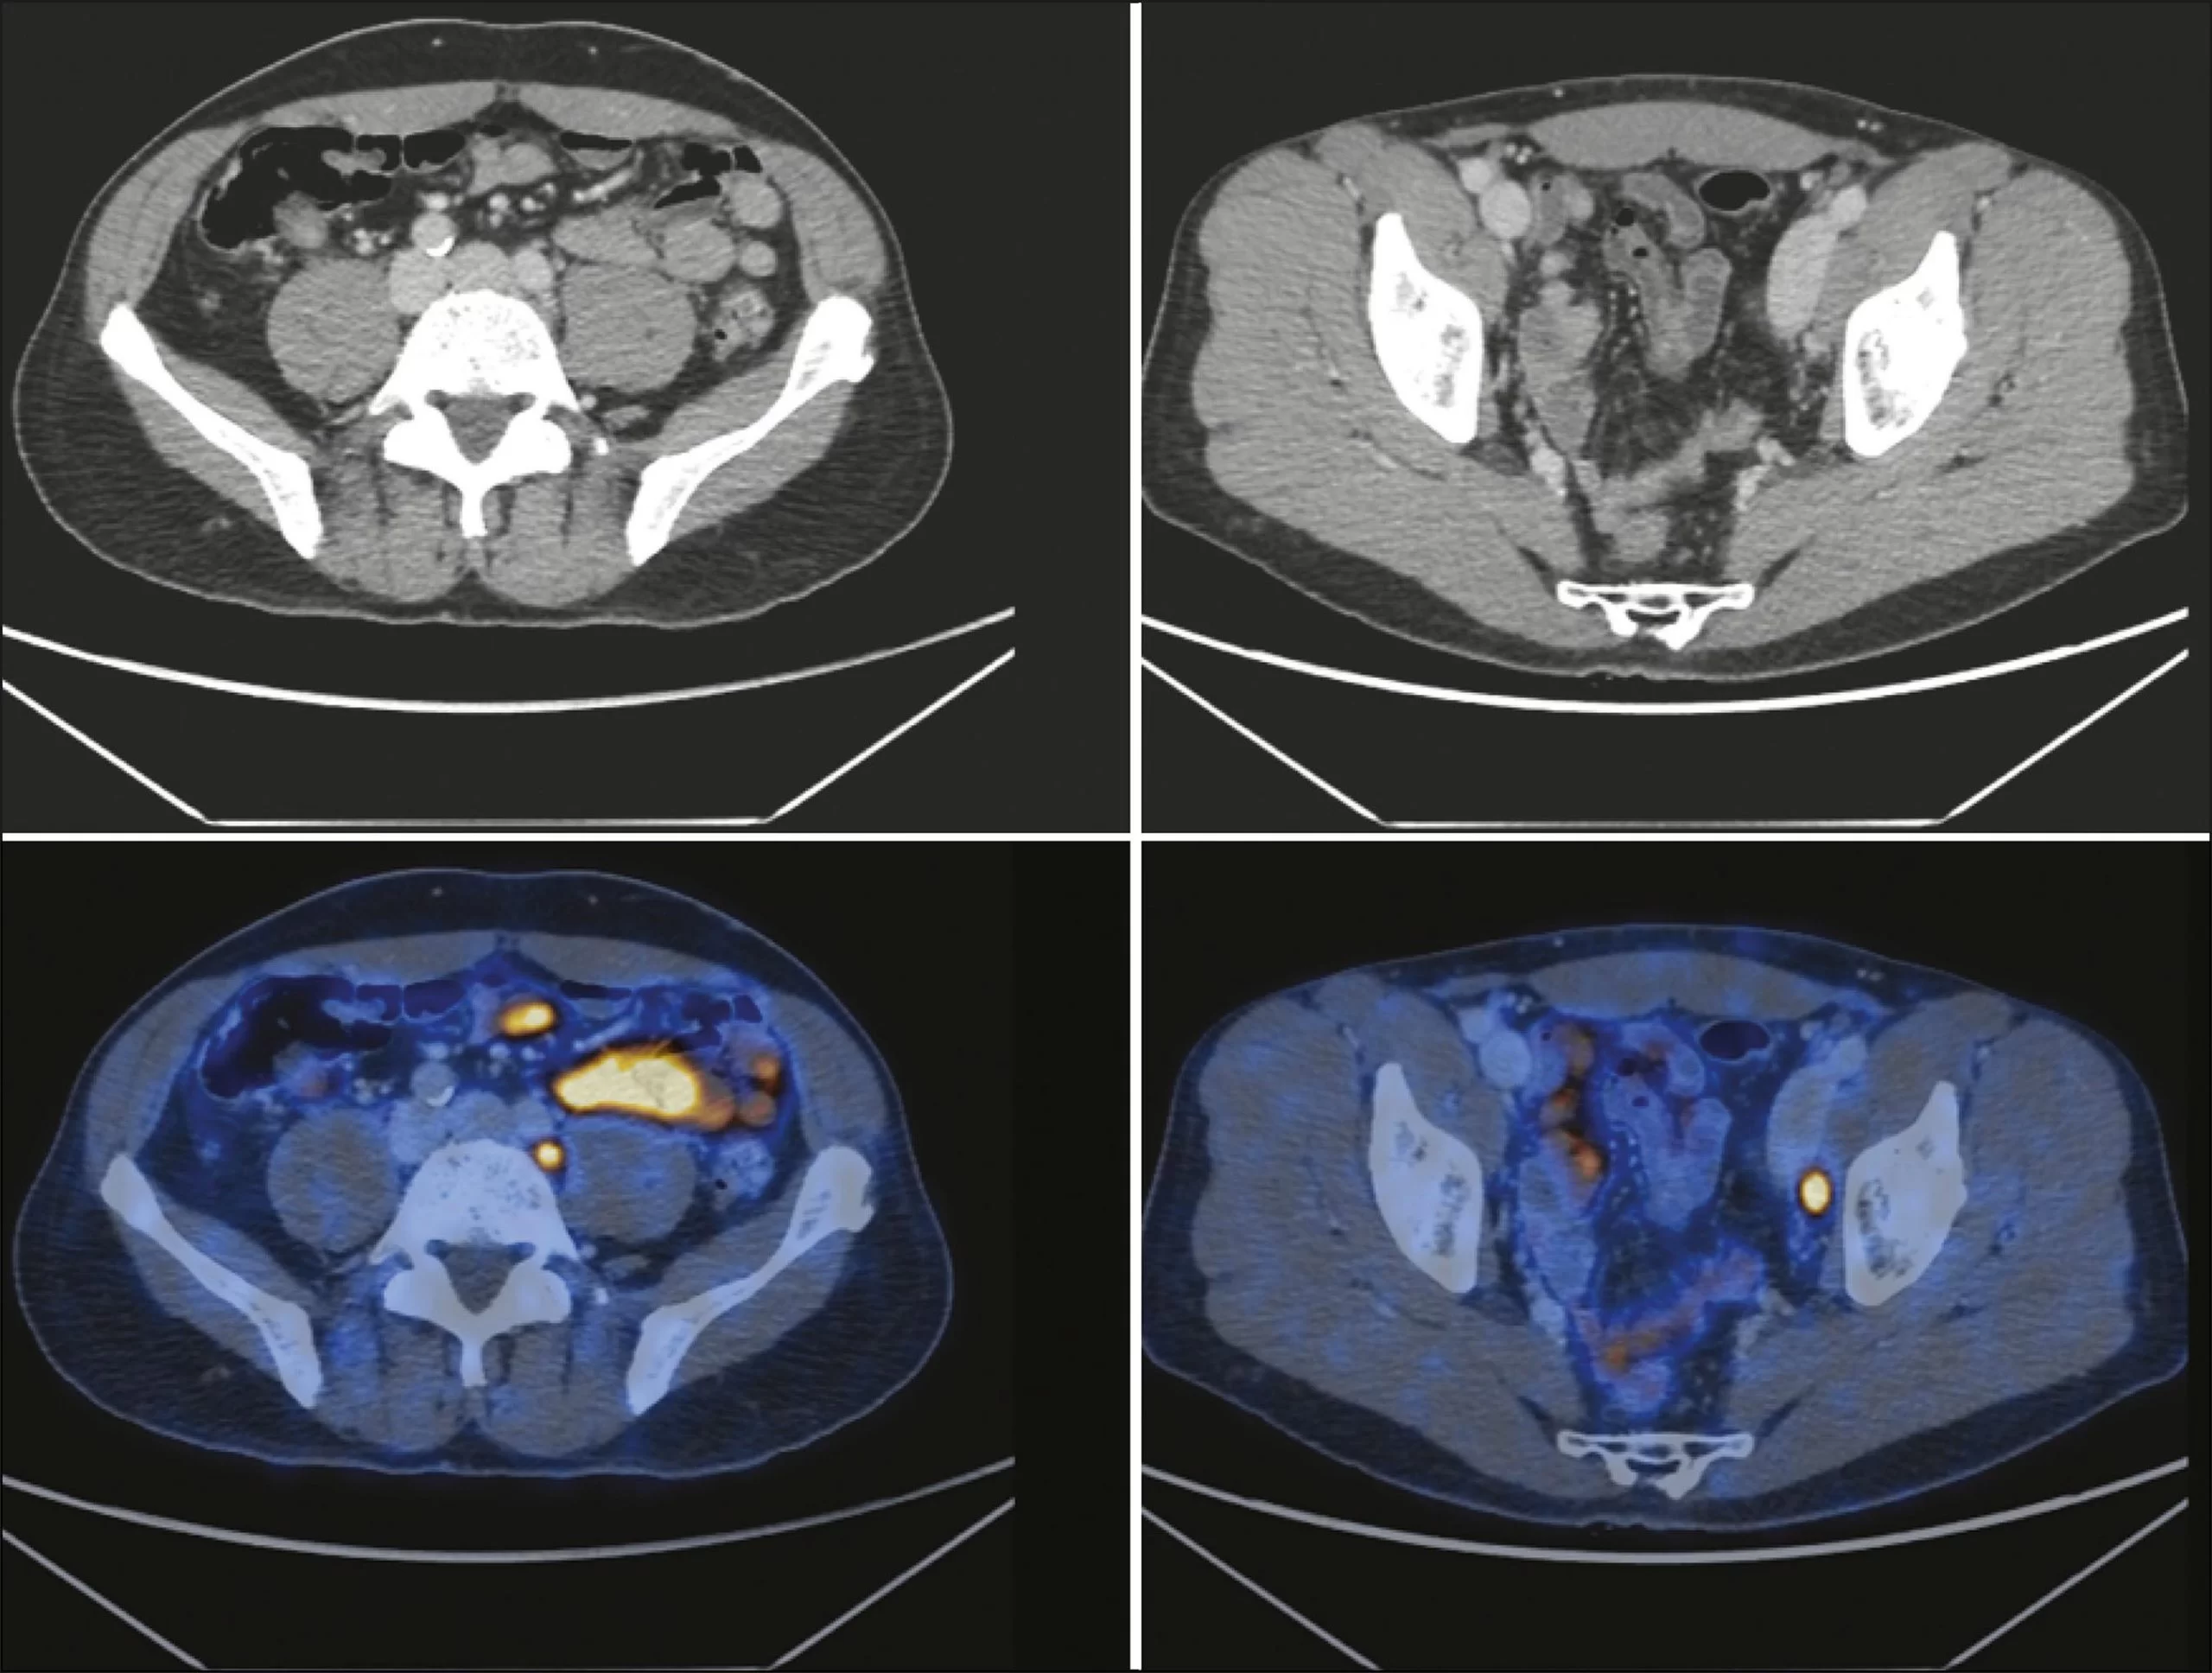

O PET-CT com PSMA (Antígeno Prostático Específico de Membrana) é uma tecnologia avançada de imagem que combina a tomografia por emissão de pósitrons (PET) com a tomografia computadorizada (CT) para a avaliação do câncer de próstata. Utilizando um radiotraçador específico para PSMA, este exame fornece informações detalhadas sobre a localização e a extensão do câncer de próstata, ajudando no planejamento e monitoramento do tratamento.

O PET-CT com PSMA é um exame de imagem que combina duas técnicas poderosas: a PET e a CT. O PSMA é uma proteína encontrada na superfície das células cancerosas da próstata. Um radiotraçador que se liga especificamente ao PSMA é injetado no paciente. A PET detecta a radiação emitida pelo traçador, enquanto a CT fornece imagens anatômicas detalhadas, permitindo a visualização precisa das áreas afetadas pelo câncer.

- Tomografia por Emissão de Pósitrons (PET): O paciente é posicionado em uma máquina PET que detecta a radiação emitida pelo radiotraçador. As imagens PET mostram a atividade metabólica nas áreas de captação do PSMA.

- Tomografia Computadorizada (CT): Imagens CT são obtidas para fornecer uma visão anatômica detalhada, que é combinada com as imagens PET para uma avaliação completa.